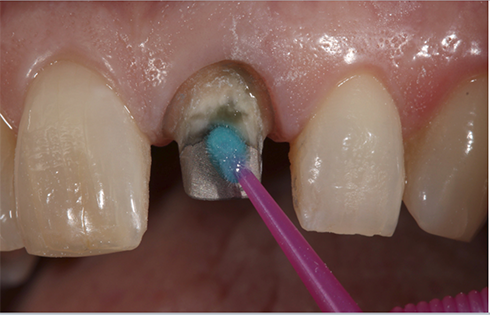

The preparation was then conditioned for 10 seconds using 20% polyacrylic acid (GC CAVITY CONDITIONER, GC America) to remove the smear layer and debris, ensure enhanced bonding to the glass ionomer cement, and if this tooth was not treated endodontically, it would have had the additional benefit of eliminating or reducing sensitivity based on its 3% aluminum chloride hexahydrate component (Fig. 9). The preparation was then rinsed and blotted dry.

Fig. 9 Fig. 10